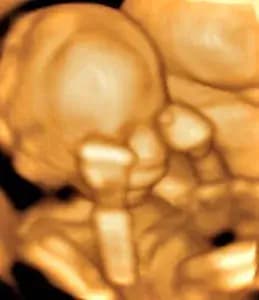

a baby human in the womb

"For you created my inmost being; you knit me together in my mother's womb."